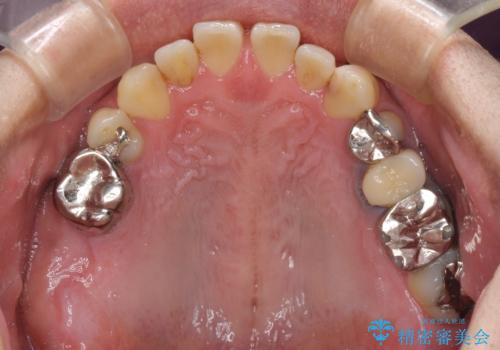

来院当初は、奥歯の銀歯が問題で咬み合わせが悪いと思っていらっしゃいましたが、前歯の反対咬合を改善することが最優先とご説明し、矯正治療を行うこととしました。

奥歯には抜歯が必要な歯があったため、事前に抜歯を行い、その後ワイヤー装置にて治療を開始しました。

今後はむし歯や銀歯を治療していく予定です。